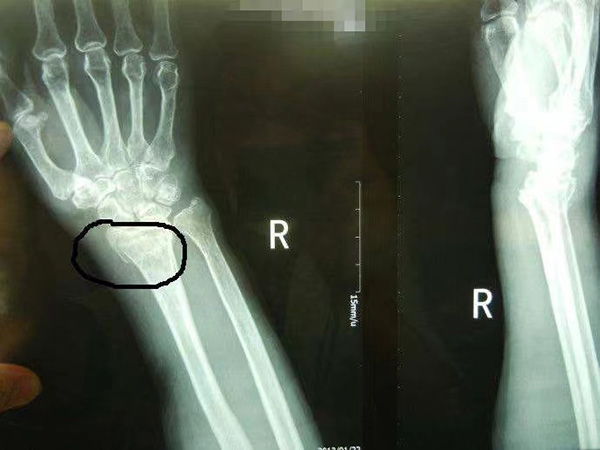

橈骨遠(yuǎn)端骨折

橈骨遠(yuǎn)端骨折是指發(fā)生在距橈骨遠(yuǎn)端關(guān)節(jié)面3cm以內(nèi)的骨折。

1. 臨床表現(xiàn):伸直型骨折即Colles骨折,多由間接暴力引起。傷后局部隨即出現(xiàn)腫脹、疼痛,可有典型畸形姿勢,側(cè)面呈“餐叉”樣畸形,正面呈“槍刺樣”畸形。查體局部壓痛明顯,可觸及骨擦音和異常活動,腕關(guān)節(jié)活動障礙,皮下出現(xiàn)瘀斑。